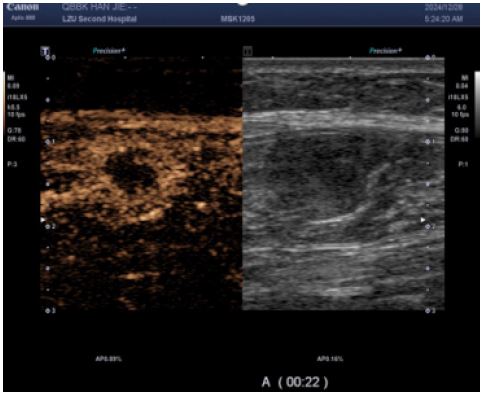

CEUS (performed next day): Demonstrated multiple hypoechoic foci in the left calf muscle layer. At 12 seconds post-contrast injection, lesions exhibited heterogeneous hyper-enhancement (> adjacent muscle tissue) with irregular non-enhancing areas.

CEUS conclusion: Enhancement pattern suggestive of benign lesions; core needle biopsy advisable.

Figure 3: CEUS suggested heterogeneous hyper-enhancement at 12 s of contrast injection.

Images are Not Display Check it

Figure 4: The enhancement borders were clear, and areas of non-enhancement were seen within them; Irregular non-enhancing areas are present throughout the enhancement pattern, consistent with a benign enhancement pattern.